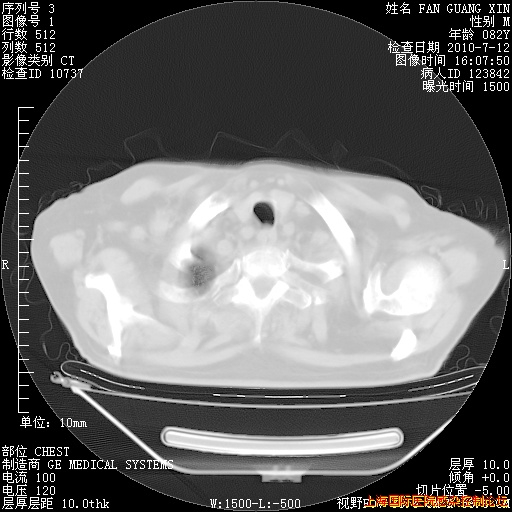

补发6月12日肺部CT肺窗

6月12日肺窗

6月12日纵膈窗